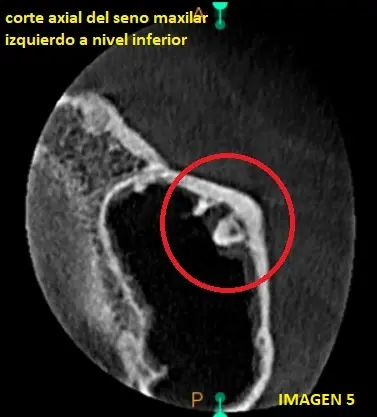

En el corte axial del seno maxilar izquierdo, a nivel inferior, podemos observar la fusion de la calcificacion, en la pared lateral del seno maxilar izquierdo, rodeada de un halo hipodenso vinculante a mucosa sinusal. (ver imagen 5)